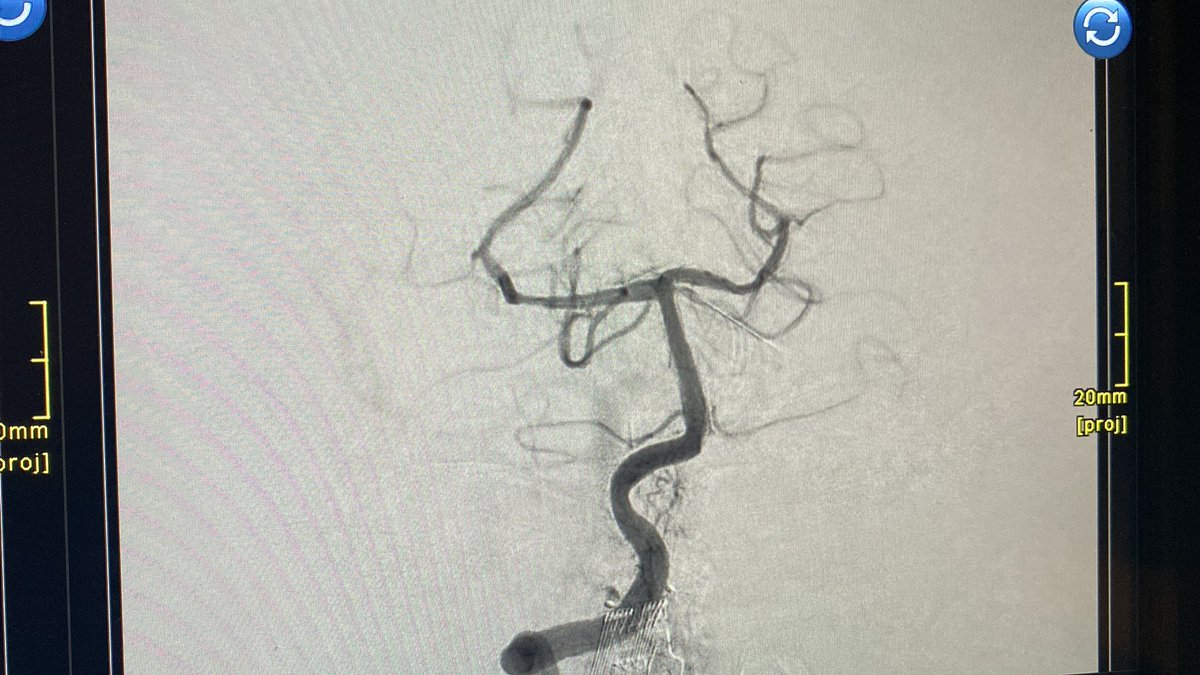

@sam_kular

4 mm Resolute Onyx stent worked well #stroke #RadialFirst

Transradial posterior circ tandem occlusion with dominant right VA stenosis